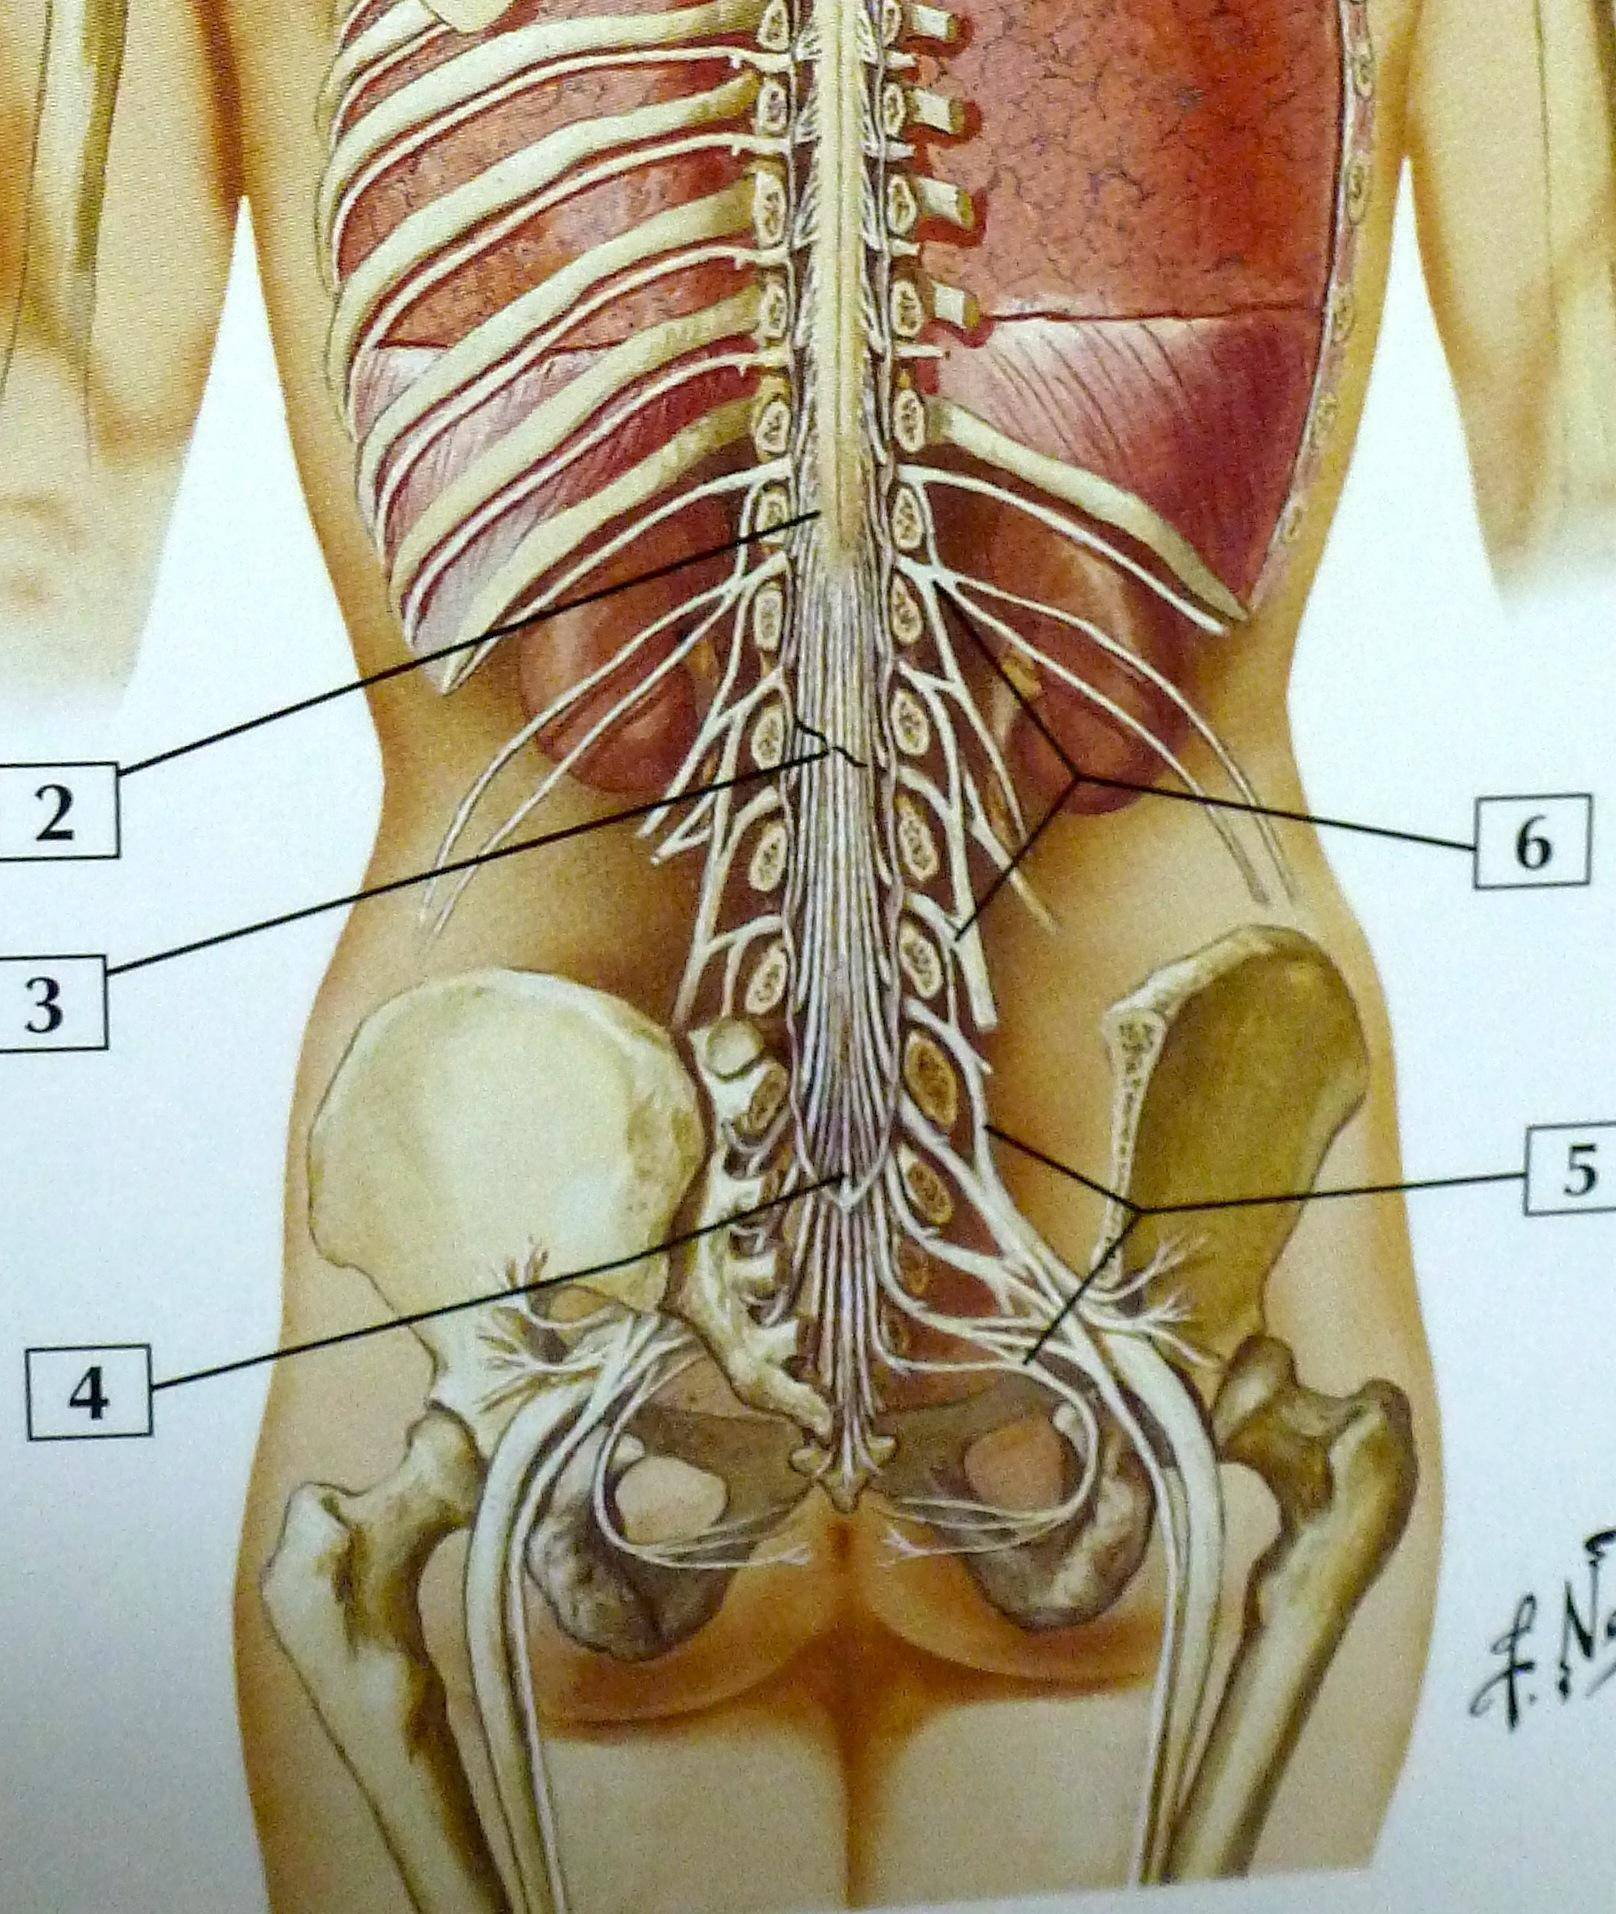

Структура позвоночника: сегменты и тазовые отделы в фотографиях